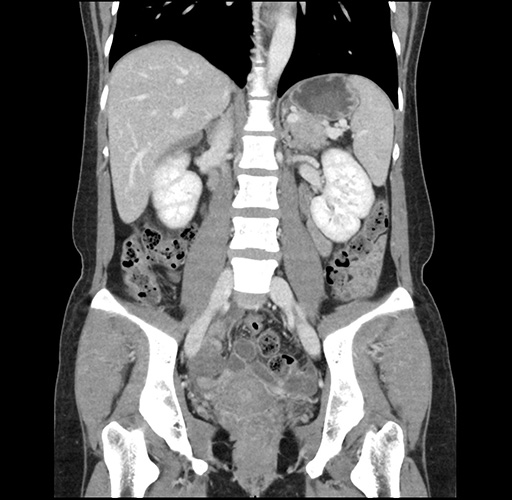

Imaging Analysis

Look through the patient's CT scan to identify any areas of concern for the necessary procedure.

Based on your CT findings, which issue(s) would give reason for "planned slowing down moment(s)" in this case?

Considering a standard left lateral sectionectomy procedure, what step(s) of the operation would you do differently in this case ?